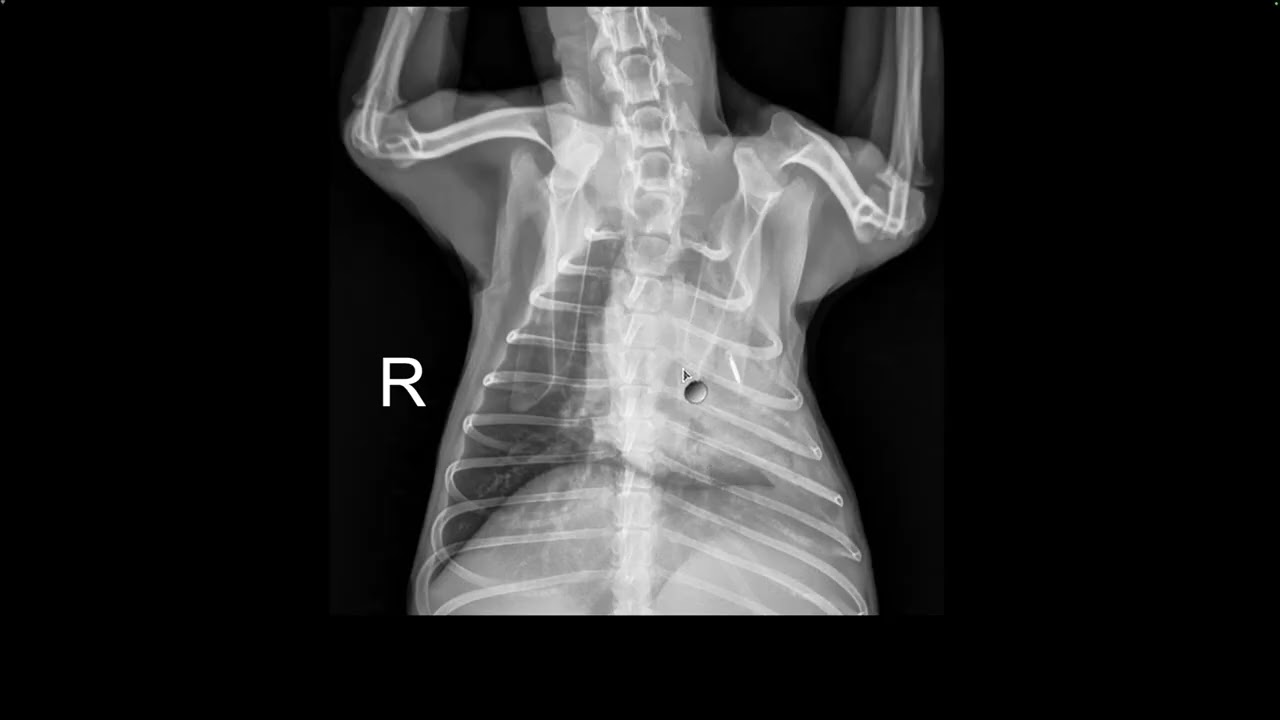

Diabetic Dog in Respiratory Distress? Here’s What the X-Ray Shows

Описание: Short tutorial walking through pneumonia findings on a canine chest X-ray in a diabetic patient.

This video is for educational purposes only and is not a substitute for professional veterinary diagnosis or treatment (but I'm a professional, very professional).